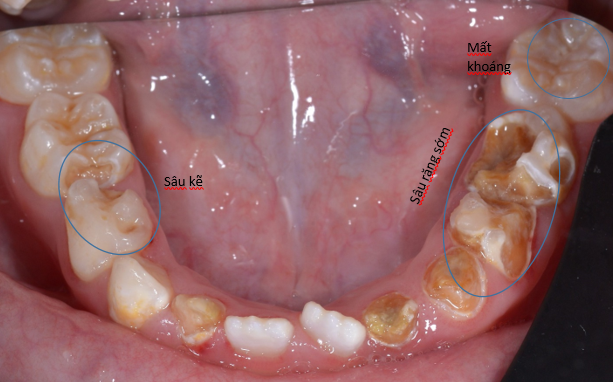

Đây là trường hợp bé 7 tuổi tới khám, bé bị sâu răng do bú bình từ nhỏ nhưng không được điều trị. Sau khi thăm khám bác sĩ đánh gía và đưa ra kế hoạch điều trị cụ thể như sau:

2. Sâu răng sớm hai hàm : mất men răng, mất mũi rãnh và hình dáng nên việc nhai thức ăn bị kém. Điều trị: trám và phục hồi với mão kim loại cho trẻ em.

3. Răng cối lớn vĩnh viễn mới mọc: có dấu hiệu mất khoáng- giai đoạn sớm của sâu răng. Cần trám phòng ngừa Sealant

5. Răng sâu kẽ làm cung răng bị mất khoảng, sau này răng vĩnh viễn mọc có thể bị chen chúc: chụp phim kiểm tra, giữ khoảng và tạo khoảng sau khi đánh giá mẫu hàm, phim.